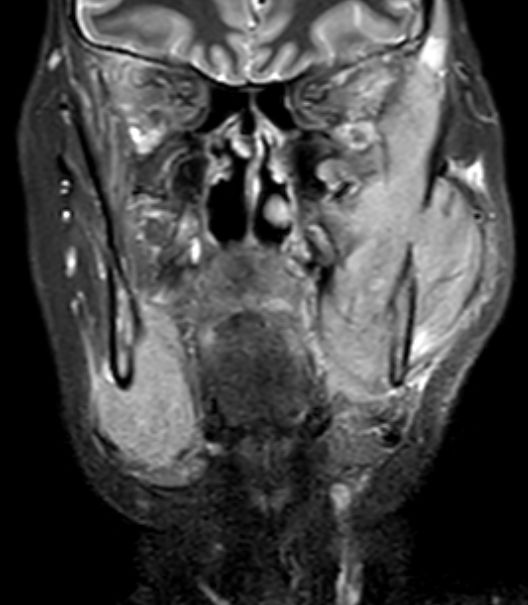

| Orbita | Das MRT zeigt eine koronare Schicht durch die Orbita mit einem extramedullären Plasmozytom ![]() | |||